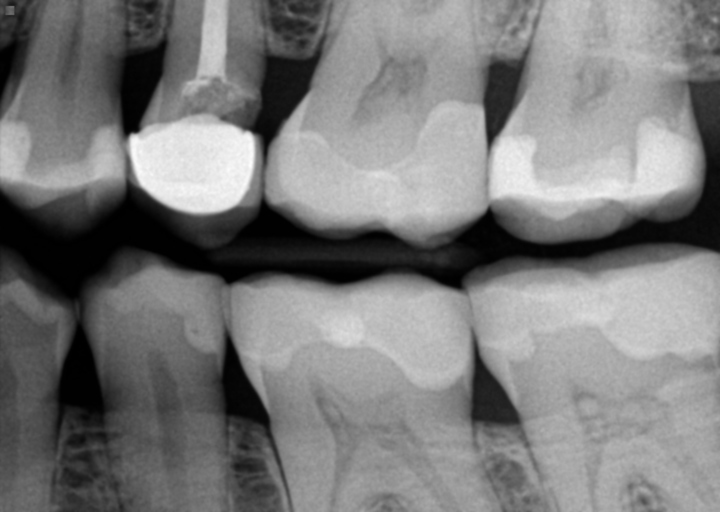

crowned tooth

I had tooth that had fillings in it from 3 different places. Back in January this year my gums on the side of that tooth became very inflamed and painful. I went to doctor who treated my cavity that was on the side but my gums wouldn't heal and with time it was going lower and lower also painful. So I went to dentist again (fully convinced I'll need a root canal) doctor took x-ray and said there is no infection so he will place a crown. I wasn't too keen on that idea but I proceed anyway.The tooth was extremely painful once I got that crown on to a point that my dentist wanted to put me on steroids !! Which I was like ...no way thats not happening...anyway after many many painkillers it calmed down the gums are visibly much lower than they were before. The problems is I can't bite on that tooth at all...I have pain every time some food gets there ...i have been walking with this since January with a crown that i paid $1300 and can't even use it ...I am in a really bad financial situation so I was convinced since I had it done that most likely I need that root canal anyway. So I just out put up with it...Recently I went to different doctor to just do cleaning and asked him if he can x-ray that tooth to see If I have an infection and he said it doesn't. He even let me keep a picture for proof. Why does it hurt if its not infected ? Does that mean that I just need bite adjustment ? I'm sacred to come back to the doctor who did that crown because I feel like he's going to try to convince me to get root canal...and I don't have the money for that...what should I do ?